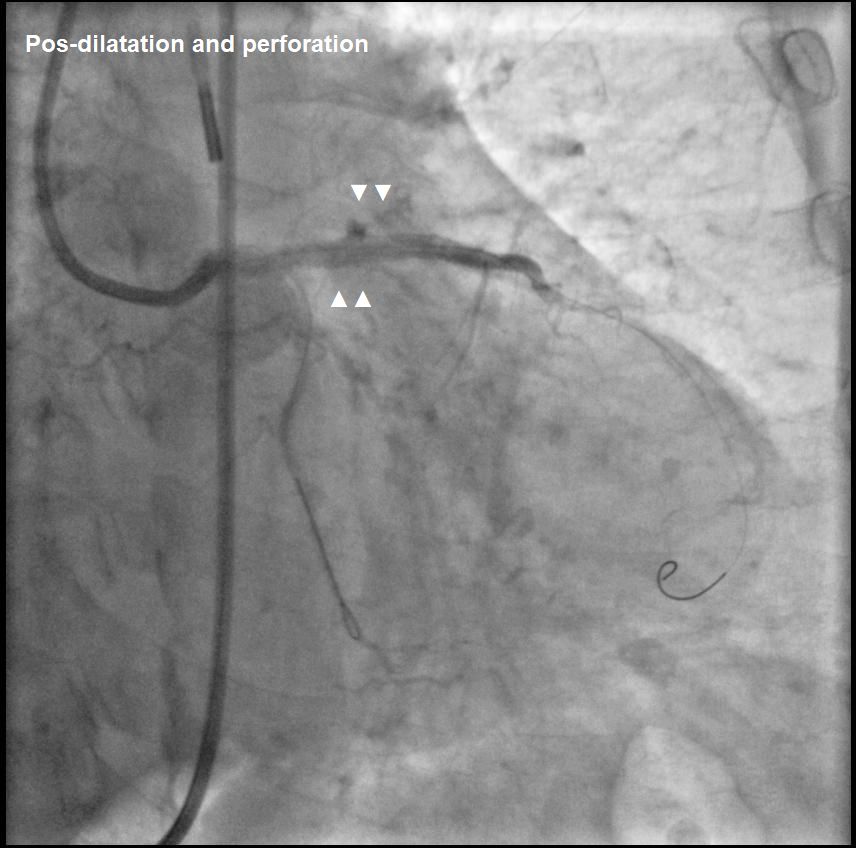

Post-dilatation with NC Sapphire 3.5 × 15 mm.Coronary perforation (Ellis III) in LAD proximal: prolonged inflation with NC Sapphire 3.5 × 15 mm. Persistent perforation treated with covered stent (Abbot Graftmaster) 2.8 × 19 mm.

Post-dilatation with NC Sapphire 3.5 × 15 mm.Coronary perforation (Ellis III) in LAD proximal: prolonged inflation with NC Sapphire 3.5 × 15 mm. Persistent perforation treated with covered stent (Abbot Graftmaster) 2.8 × 19 mm.

Guidewire entrapment during PCI is rare. In this case, the complication began with stent malapposition in the LAD, followed by post-dilatation that led to vessel perforation. During prolonged balloon inflation, the LCx wire was inadvertently pulled into the LAD, leading to guidewire entrapment when a covered stent was placed. Direct retrieval using a microcatheter was not possible, requiring surgery to cut the guidewire at the LM ostium, with the remaining LCx wire covered by a stent.